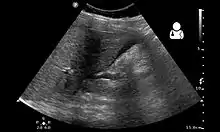

Ultrasound showing a heterotopic pregnancy (intrauterine + extrauterine pregnancies) with signs that the extrauterine (ectopic) pregnancy has ruptured.[1]

The gold standard for diagnosing a heterotopic pregnancy is the transvaginal ultrasound. However, the sensitivity of the transvaginal ultrasound for diagnosing a heterotopic pregnancy has been found to range from 26.3% to 92.4%.[5] Therefore, both clinical symptoms and ultrasound imaging are used to make the diagnosis.